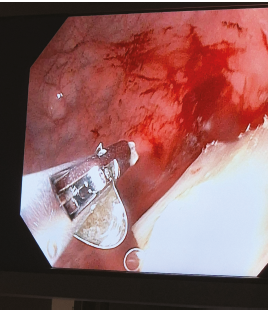

Lékaři z Pediatrické kliniky 2. LF UK a FN Motol varují před ostrými kovovými součástmi produktů pro užívání zahřívaného tabáku, které mohou být nebezpečné pro nejmenší. Drobné části těchto výrobků se snadno uvolňují a v domácnostech, kde se pohybují děti, se mohou během vteřiny stát rizikovým předmětem.

Zatímco dospělí vnímají produkty pro užívání zahřívaného tabáku jako moderní alternativu ke klasickému kouření, pro děti mohou představovat závažné zdravotní riziko. Pediatrická klinika 2. LF UK a FN Motol v uplynulém roce hospitalizovala deset dětí ve věku od osmi do patnácti měsíců, které pozřely ostrý kovový plíšek pocházející z těchto produktů.

U tří malých pacientů bylo nutné provést urgentní endoskopický zákrok, díky němuž se podařilo předejít nutnosti chirurgického výkonu.